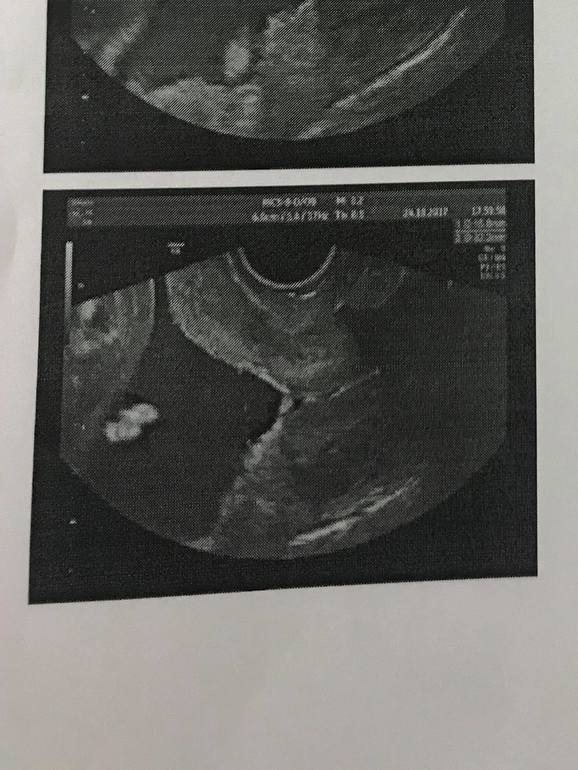

Внутренний зев